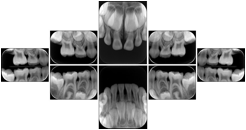

Intra-oral radiography typically involves acquisition of multiple images of various parts of the dentition. Many digital radiographic systems offer customized templates that are used for displaying the images in a study on the screen. These templates may also be referred to as mounts or view sets. The Structured Display Object represents a standard method of encoding and exchanging the layout and intended display of Structured Displays. A structured display object created in this manner could be stored with a study and exchanged with images to allow for complete reproduction of the original exam.

3. A dental provider wishes to capture a series of DICOM IO images for the patient’s dentition. The tooth morphology, teeth are divided into molars, premolars, canines and incisors, and a number of images for each jaw. The anatomic information was captured utilizing the triplet of schema. This standard code sequence is based on ISO 3950-2010, Dentistry - Designation system for teeth and areas of the oral cavity.

Every IO image should have anatomic information either through the primary or modifier sequence.

In most standard cases, images are oriented in structured layouts. These structured displays are useful to be shared between providers for reference purposes.

Table OO.1.1-1 shows structured display standard templates, where Viewset ID is based on the Japanese Society for Oral and Maxillofacial Radiology (JSOMR) classification provided by JIRA (Japan Medical Imaging and Radiological Systems Industries Association, www.jira-net.or.jp). Expected or typical teeth to be imaged location, region and designation codes are based on ISO 3950-2010, Dentistry - Designation system for teeth and areas of the oral cavity. For all the hanging protocols listed in OO.1.1-1, the value to use for Hanging Protocol Creator (0072,0008) is "JSOMR" and the value to use for Hanging Protocol Name (0072,0002) does not include "JSOMR" (e.g., "DL-S001A", not "JSOMR DL-S001A").